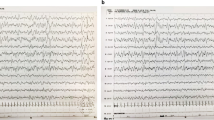

The analysis is based on a four-generation family. The unaffected male of the core family (III.5 in Fig. 1) has four sibs all affected with microcephaly, intellectual disability, and the characteristic facial aspect of autosomal recessive primary microcephaly (sloping forehead, micrognathia). Two of them also exhibit short stature, two were in the lower normal range. All attended a school for mentally handicapped and were able to speak in sentences (Table 1).

The unaffected III.5 has together with his cousin III.6 eight offspring, among them four fetuses with severe primary microcephaly diagnosed in the first trimester of pregnancy by ultrasound. All four affected fetuses presented with microcephaly and retrognathia already present at 15 gestational weeks. A detailed autopsy of the fetal brain of IV.2 showed an extensive migration impairment of the cerebral hemispheres, a developmental disorder of the hippocampal formation and hypoplasia of the cerebellar hemispheres. The pregnancies with the affected fetuses were terminated on maternal psychological grounds.

Thus, all affected individuals are compound heterozygous for the novel PLK4 variant (c.881 T > G) and the deletion covering PLK4 (Fig. 2). The four affected adult patients of generation III reported here have a remarkably mild clinical phenotype compared to individuals with previously described PLK4 mutations. The latter show more severe microcephaly (up to – 15 SD) and short stature (up to – 8 SD), whereas two of our patients exhibit only mild short stature (III.3, III.4), two were in the lower normal range. Furthermore, our patients have only moderate Intellectual disability as all have attended a school for mentally handicapped. In particular their verbal skills are noteworthy, since all were able to speak in sentences, while the patients described in the literature have no speech or can speak only single words. Most reported patients have variable ophthalmological anomalies including retinopathy, microphthalmia, and optic nerve hypoplasia. A detailed ophthalmological examination could not be performed on our patients.